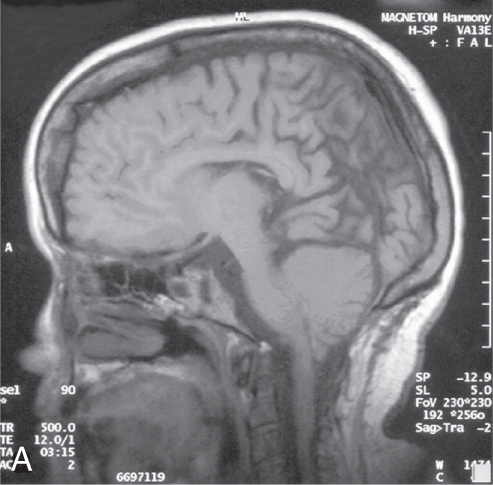

Dị tật Arnold-Chiari II (A-C II) (Hình 48.7)

Rỗng tủy (Hydromyelia) (Hình 48.7)

Hình 48.7 MRI Dị tật Arnold-Chiari II (A-C II)

(Hình ảnh MRI (A) cho thấy dị tật Chiari II và (B) cho thấy rỗng tủy)

- Dị tật Chiari II có triệu chứng vẫn là nguyên nhân gây tử vong hàng đầu cho trẻ sơ sinh bị MMC.

- Rỗng tủy (Hydromyelia): Sự giãn nở của ống trung tâm tủy sống. Khi có triệu chứng, nó thường biểu hiện bằng vẹo cột sống tiến triển nhanh, thay đổi sức mạnh hoặc phối hợp của chi trên hoặc chi dưới, và co cứng. MRI là xét nghiệm tốt nhất để chứng minh bất thường tủy sống này.